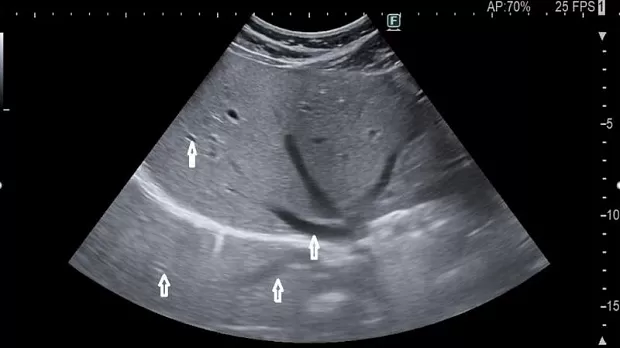

Акустическое затемнение (акустическая тень) – весьма полезный артефакт, который помогает диагностировать кальцинированные поражения (желчные и мочевые камни)[5]. Проявляется это возникновением темной области без какого-либо сигнала дистальнее затеняющего объекта. Примером может служить эффекты возникающие при неадекватном акустическом контакте баллона эхоэндоскопа со слизистой оболочкой стенки полого органа (недостаточное наполнение баллона, недостаточное количество жидкости в просвете органа, некачественная подготовка слизистой перед исследованием) когда на фоне возникающих артефактов реверберации, могут наблюдаться эффекты акустических теней.

Рис.5 Множественные гиперэхогенные камни желчного пузыря с дистальной акустической тенью